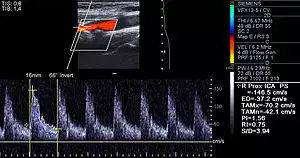

Doppler ultrasound of right internal Carotid artery with calcified and non-calcified plaques showing less than 70% stenosis

Lumen stenosis that is greater than 75% was considered the hallmark of clinically significant disease in the past because recurring episodes of angina and abnormalities in stress tests are only detectable at that particular severity of stenosis. However, clinical trials have shown that only about 14% of clinically debilitating events occur at sites with more than 75% stenosis. The majority of cardiovascular events that involve sudden rupture of the atheroma plaque do not display any evident narrowing of the lumen. Thus, greater attention has been focused on "vulnerable plaque" from the late 1990s onwards.[69]